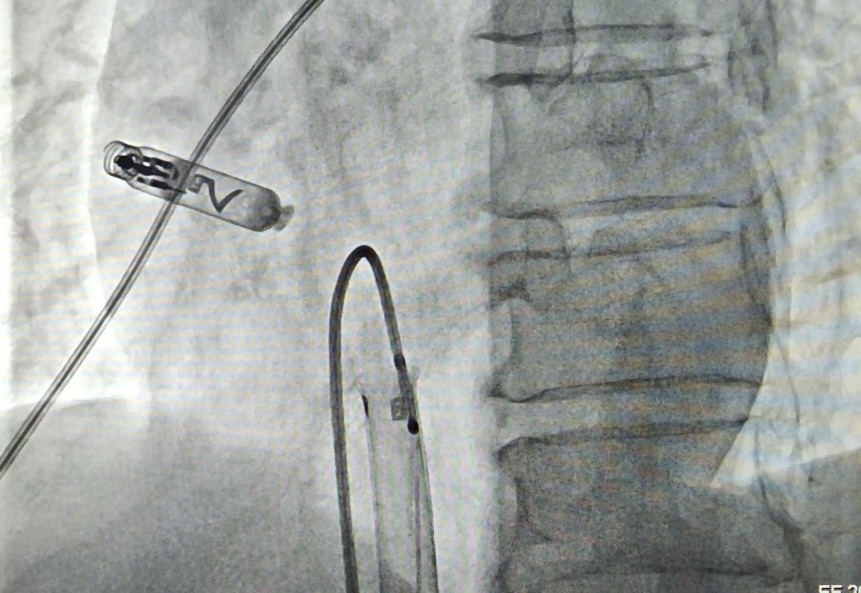

手术中,曲新凯与孔琤琦副主任医师通过患者大腿根部的股静脉,将起搏器顺利送至心脏右心耳——这里是心房最合适的起搏位置。借助起搏器头端的双螺旋设计,医生将其像螺丝一样轻轻旋入心耳组织,实现牢固“锚定”。整个手术过程不到一小时,术后测试显示起搏器工作一切正常。